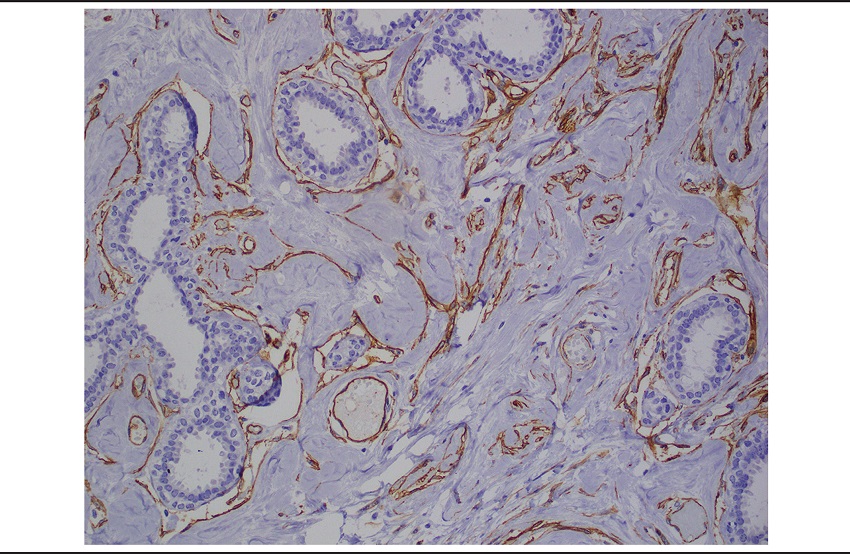

On the first post-operative appointment, pathology review of the case was requested by the clinical team. At that time, immunohistochemical staining was performed and showed that the spindle cells were positive for CD34 (Figure 5) and negative for actin. Both estrogen receptor (ER) and progesterone receptor (PR) showed positivity in breast epithelium with only focal weak staining in breast stroma and spindle cells lining slit-like spaces. Ki-67 showed low proliferation index (< 1%). Based on this immunohistochemical profile, the original diagnosis of the left breast tumor was amended to nodular PASH with fibroadenomatoid hyperplasia and stromal myxoid changes.

The histologic appearance of PASH is variable, from slender cords of myofibroblasts with few recognizable spaces to prominent anastomosing spaces in a complex configuration. In this case the spaces were obvious throughout the stroma. Myofibroblastic cells that line the slit-like spaces of PASH show variable expression of myoid and fibroblastic markers. They are usually reactive for CD34 and vimentin, with variable expression of smooth muscle actin and calponin(6). They lack immunoreactivity to keratins and endothelial markers such as CD31 and factor VIII. The nuclei can be positive for PR but are almost always negative or weak and focal for ER(6). In this case, myofibroblasts were diffusely positive for CD34, negative for actin and negative for ER and PR, consistently with what is expected for PASH.